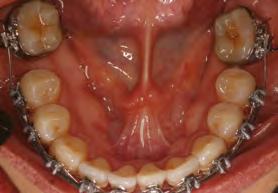

en paciente adulto tratado con extracciones de primeros molares permanentes. Reporte de caso

Dentista y Paciente 52 Sonriendo al futuro

Extraer los primeros molares permanentes puede ser una opción de tratamiento en ciertos casos de ortodoncia, como aquellos con apiñamiento moderado, biprotrusión, mordidas abiertas, o problemas de clase II y III que requieran extracciones. Además, se considera esta opción cuando los primeros molares están afectados por caries extensas u otras afecciones, lo que los hace más adecuados para la extracción y evita tratamientos restaurativos extensos o la necesidad de implantes en el futuro. Este artículo presenta el caso de una paciente en el que se optó por extraer los primeros molares superiores e inferiores para lograr resultados clínicos óptimos tanto en términos faciales como oclusales.

Palabras clave: extracción, primer molar, maloclusion, tratamiento ortodoncia.

Las extracciones dentales en los tratamientos de ortodoncia pueden ser indicadas en casos de caries extensas, restauraciones deficientes y/o extensas en premolares sanos, patologías periapicales, apiñamiento posterior y mordidas abiertas anteriores. La extracción de primeros molares permanentes es uno de los muchos planes de tratamiento en algunos casos de ortodoncia, en los cuales se presentan situaciones donde los primeros molares se encuentran comprometidos por lesiones cariosas extensas o alteraciones del desarrollo, por lo cual pueden ser candidatos para ser extraídos en casos donde se realizará tratamiento ortodóntico de pacientes como en los que se presentan apiñamiento moderado, biprotrusión, mordidas abiertas, clase II y III, casos en los cuales es necesario realizar exodoncias. Las extracciones posteriores producen una rotación antihoraria mandibular lo que podría ser conveniente en pacientes cuyas características faciales no se deben comprometer, como en pacientes con ángulo nasolabial obtuso, donde una significativa retracción de los dientes anteriores podría causar mayor apertura de este, lo que representaría en un resultado estético negativo y en camuflaje de pacientes clase II esqueléticas (extracciones superiores) y III (extracciones inferiores).1

189. Mayo 2024 53 Tratamiento ortodóncico

Cerrillo Lara Daniel. Ibarra Ramiro Jaime Tadeo. José de Jesús Anaya. Universidad Autónoma de Baja California. Campus Tijuana. Especialidad en Ortodoncia

Reporte del caso

Paciente del sexo femenino de 39 años de edad, sin datos patológicos aparentes, acude a la clínica de ortodoncia de la Facultad de Odontología campus Tijuana en diciembre del 2016. Su motivo de consulta fue: "Tengo el diente de abajo mal acomodado" En las fotografías extraorales se observa un paciente mesomorfo, biotipo mesoprosopo, línea superciliar asimétrica, línea bipupilar simétrica, nariz asimétrica, línea comisural asimétrica, labios medianos, tercio inferior aumentado respecto al medio y superior. Presenta perfil convexo, con un ángulo nasolabial obtuso (100°), surco mentolabial (122°). Línea dental superior desviada hacia la izquierda con respecto a línea media facial, muestra 100% de coronas dentales al sonreír. En el análisis intraoral se observa dentición permanente, líneas medias no coincidentes, microfracturas de OD #11 Y #21, clase molar indeterminada bilateralmente por ausencia de OD #16 Y #26, clase I canina bilateral, forma de arcada ovoide en superior, apiñamiento leve, #11, #12, #21 mesiorotados y #25 distorotado, forma de arcada ovoide en inferior, apiñamiento leve y OD #41 lingualizado, presencia de torus mandibular. Sobremordida horizontal de 2 mm y vertical de 20%. En el análisis radiográfico se muestran 26 dientes presentes en boca, ausencia de OD #16 y #26, presencia de #18, #28, #38 y #48 retenidos, altura de ramas mandibulares simétricas, densidad ósea

uniforme, relación corona-raíz 1:1; se observa además una maloclusión clase II esquelética, con crecimiento vertical, dientes anteroinferiores proinclinados así como los anterosuperiores.

Objetivos del tratamiento

Mejorar perfil del paciente, lograr clase molar I bilateralmente con mesialización de #37 y #47, después de extraer primeros molares mandibulares, mantener clase I canina bilateralmente, así como las sobremordidas vertical y horizontal, eliminar apiñamiento, corregir líneas medias, obtener oclusión funcional.

Plan de tratamiento interdisciplinario

Se remite al área de cirugía de la facultad de Odontología para extracciones de los OD #36 y #46 con el fin de armonizar la arcada inferior con la arcada superior, para después proceder a la mesialización de OD #37 y #47.

Plan de tratamiento ortodóncico

Se colocó aparatología fija superior e inferior tipo Alexander slot 0.022, se prosiguió a la alineación y nivelación, expansión superior e inferior con secuencias de arcos, mesialización de OD #37 y #47, recontorneo interproximal inferior, torque de raíces, armonización de arcadas, extracción de terceros molares inferiores y valoración de los superiores, retención removible superior e inferior.

Dentista y Paciente 54 Sonriendo al futuro

Figura 1. Fotografías extraorales de frente y de perfil. Figura 2. Fotografías intraorales iniciales.

Resultados

Se obtuvieron los resultados mencionados al inicio como clase I molar y canina, sobremordidas adecuadas, eliminación del apiñamiento, corrección de líneas medias y una oclusión funcional.

Discusión

La prevalencia de las extracciones dentales en los tratamientos de ortodoncia ha variado a lo largo de los años y esto es corroborado por 40 años de estudios retrospectivos llevados por Proffit, quien demuestra que durante los años 50 el porcentaje de

extracciones aumentó en un 10%, en los 60 en un 50 % y para los años 80 observó una reducción del 35%, al igual que para Peck y Peck que fue del 32% en ambos arcos.2-3

La extracción de algún diente siempre ha sido tema de discusión y aún más cuando son extracciones de primeros molares, ya que en un tratamiento por lo regular se considera que estos órganos dentarios son llaves fundamentales de la oclusión; sin embargo, Pérez en 2015 afirma que el tratamiento con extracciones de primeros molares tiene resultados positivos en el perfil, tal como

189. Mayo 2����2�� 55 Tratamiento ortodóncico

Figura 3. Modelos de estudio iniciales. Figura 4. Ortopantomografia inicial. Figura 5. Figura 6. Fase de alineación y nivelación.

sucedió en este caso y los reportados por Bahoquez en 2015. Rey en 2012 menciona también aquí resultados favorables al extraer los primeros 4 primeros molares a pesar de ser considerados piezas claves en la oclusión.4-5

Conclusión

La extracción de los primeros molares se presenta como una alternativa

efectiva para abordar casos de mordida abierta esquelética, perfiles convexos, rotación horaria de mandíbula entre otros, logrando resultados estables, funcionales y estéticamente satisfactorios. Es crucial destacar que esta decisión terapéutica requiere una cuidadosa elección de casos, así como una habilidad clínica y experiencia considerable para asegurar que las expectativas y resultados del tratamiento no se vean comprometidos.6

Dentista y Paciente 56 Sonriendo al futuro

Figura 7. Cierre de espacios superior e inferior. Figura 8. Retracción del segmento anterior. Figura 9. Fotografias intraorales finales.

Referencias

1. Rey D, Oberti G, Sierra A. Extraccion del primer molar permanente como una alternativa en el tratamiento de ortodoncia. Rev. CES Odont. 2012;25(1) 44-53.

2. Proffit WR. Forty-year review of extraction frequencies at a university orthodontic clinic. Angle Orthod. 1994;64(6):407–14.

3. Peck S, Peck H. Frequency of tooth extraction in orthodontic treatment. Am J Orthod. 1979 nov;76(5):491–6.

4. G. (2015). Tratamiento de mordida abierta con extracciones de primeros molares. Reporte de caso. Revista Mexicana de Ortodoncia, 3(4), 266–273.

5. Bahoquez, A. (2015). Exodoncias de primeros molares y verticalización de tercer molar inferior en paciente con mordida abierta, reporte de caso. Revista Latinoamericana de Ortodoncia y Odontopediatria.

6. Seddon JL. Extraction of four first molars: a case for a general practitioner? J Orthod. 2004 jun; 31(2):80-5.

7. Daugaard-Jensen I. Extraction of first molars in discrepancy cases. Am J Orthod. 1973 ago;64(2):115– 36.

8. Williams R. Single arch extraction--upper first molars or what to do when nonextraction treatment fails. Am J Orthod. 1979 oct;76(4):376–93.

189. Mayo 2����2�� 57 Tratamiento ortodóncico

Figura 10. Fotografias intraorales finales. Figura 11. Radiografía lateral de cráneo final. Figura 12. Fotografias extraorales finales.

Mucho cuidado con los equipos de rayos X intraorales portátiles

¿Está justificada esta advertencia?

Dentista y Paciente 58 Boletín

La redacción

En Dentista y Paciente queremos que los odontólogos conozcan el riesgo que implica el uso indebido de fuentes de radiación ionizante.

Los equipos portátiles están diseñados para llevar a cabo una exposición con el operador sujetando el equipo con ambas manos, y debido a la imposibilidad de alejarse del mismo a la distancia reglamentada, el operador se encontrará expuesto a una dosis de radiación ionizante once veces mayor, siendo esto el mejor de los casos.

Estamos conscientes de que la mayoría de los odontólogos ignoran los riesgos que implica el uso de fuentes de radiación, los cuales aumentan con la frecuencia y dosis de la misma, es por eso que nuestro deber nos llama a advertir al odontólogo para prevenir antes que lamentar.

En la literatura sobre la seguridad radiológica con equipos intraorales portátiles, hemos observado un creciente número de opiniones negativas sobre el uso de equipos diseñados para que el operador los sujete con sus manos para poder llevar a cabo así, una toma radiográfica periapical.

Esto implica que, de utilizarse el equipo portátil en el consultorio dental, el odontólogo tendrá en sus manos la fuente generadora de radiación, algo

189. Mayo 2024 59 Mucho cuidado con los equipos de rayos X intraorales portátiles

que no estaba previsto en la Norma Reguladora de Seguridad Radiológica NOM-229-SSA1-2002 (https:// www.gob.mx/cms/uploads/attachment/file/839898/IB_NOM229_ Infografia_24-03-2023_light.pdf), misma que excluyó de su campo de aplicación los equipos de rayos X convencionales, por considerar que los equipos de rayos X periapicales fijos tradicionales no presentarían mayores riesgos sanitarios al ser utilizados con los protocolos de seguridad sugeridos por ALARA, ICRP y otras instituciones, mismas que recomiendan mantener una distancia mínima de 2 metros entre el operador y la fuente generadora de rayos X, al efectuar el disparo mediante un disparador con cable retráctil, o con la opción de instalar un disparador remoto fuera del cuarto radiográfico.

Muchos odontólogos ignoran o subestiman los daños de tipo determinísticos o estocásticos, que son los causantes de provocar alteraciones cromosómicas a la célula, esto debido al uso indebido de fuentes

Muchos odontólogos ignoran o subestiman los daños de tipo determinísticos o estocásticos, que son los causantes de provocar alteraciones cromosómicas a la célula, esto debido al uso indebido de fuentes generadoras de radiación ionizante, pues aquellos que no lo saben suelen considerar al equipo portátil un avance tecnológico, cuando en realidad estos productos fueron diseñados para otras aplicaciones, al considerar que en sus países de origen su uso en el consultorio dental está restringido por normas de seguridad radiológica, debido a la imposibilidad para el operador de alejarse de la fuente de radiación, exponiéndose así a una dosis de radiación ionizante, por radiación dispersa y de fuga, mucho mayor de la que recibiría con un equipo fijo tradicional, al aplicar los protocolos antes mencionados.

Dentista y Paciente 60 Boletín

En la literatura sobre la seguridad radiológica con equipos intraorales portátiles, hemos observado un creciente número de opiniones negativas sobre el uso de equipos diseñados para que el operador los sujete con sus manos para poder llevar a cabo así, una toma radiográ����ca periapical��

1. RAGGI X IN MEDICINA-FISICA- TECNICA-APPLICAZIONI. Ed. GILARDONI S.p.A. 2.1.4.

2. ODOVTOS – Actualización en equipos de Rayos X portátiles en odontología. Lucía Barba Ramírez DDS, Deivi Cascante Sequeira DDS. Publicado en línea : 15-II-2021. Recuperado de: https://www.scielo.sa.cr/pdf/odovtos/v24n2/2215-3411-odovtos- 24-02-26.pdf

3. Revisión de las principales normas de protección radiológica para el uso de equipos de Rayos-X en odontología. Recuperado de: https://revistas.cientifica.edu.pe/index.php/ odontologica/article/download/538/6 19/